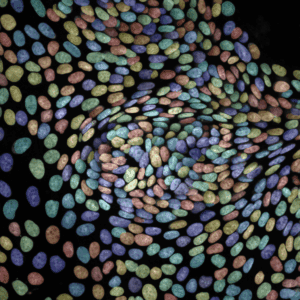

ProxyDiscovery provides patient-derived organoid models that mirror real tumor biology. By generating functional readouts of drug response, we enable more accurate predictions of clinical outcomes and guide better decision-making at every stage of discovery.

We test lead compounds across diverse patient populations to capture variability in response. Through predictive modeling of therapeutic windows and safety profiles, we help identify patient subgroups most likely to benefit, reducing risk and improving outcomes.

We enable smarter clinical trial design through patient stratification, biomarker identification, and companion diagnostic development. By enriching trial populations and predicting likely responders, we help increase trial efficiency and improve the probability of clinical success.